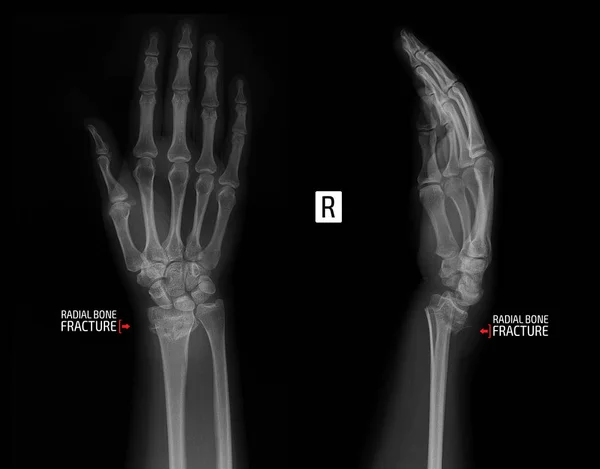

1 . Рентгенография при переломе луча в типичном месте • Перелом Бартона: о Внутрисуставной перелом края лучевой кости о Может быть тыльным или ладонным (обратный перелом Бартона) о Фрагмент лучевой кости и кости запястья смещаются вместе как одно . . .

Переломы дистального отдела лучевой кости руки являются наиболее распространенными переломами предплечья и составляет около 16% от Рентген анатомия лучезапястного сустава Наклон суставной поверхности лучевой кости в прямой проекции в норме составляет 15-25º .

Самым частым травматическим повреждением костей верхних конечностей является перелом луча в типичном месте . Нарушение целостности нижнего конца лучевой кости, расположенного в непосредственной близости с кистью, считается несложной травмой .

Все достаточно просто: это участок кости примерно в 2 см от края со стороны кисти, там кость ломается легче и чаще всего, поэтому такие переломы часто называют переломами луча в типичном месте .